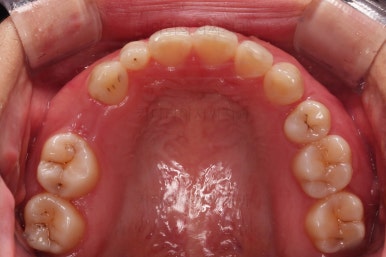

부산인비절라인 초진 시 얼굴모습 입니다.

언뜻 보면 치열도 가지런해 보이고 나쁘지 않죠?

대신 자세히 보면 윗니의 중앙이 얼굴기준 오른쪽으로 돌아가는 걸 볼 수 있습니다.

보통 중앙은 인중~윗입술 중앙을 연결하는 가상의 중앙선과 일치하면 가장 좋은데요.

이번 환자분은 어떤 이유에서인지 우측으로 매우 틀어져 있었어요.